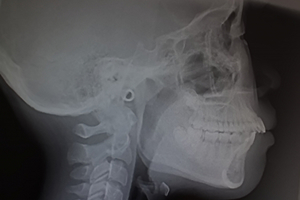

1.CT・セファロを用いた

精密診断

矯正治療を正確に進めるためには、骨格や歯の位置関係を詳細に把握することが欠かせません。そこで当院では、CT撮影やセファロ(頭部X線規格写真)を活用し、立体的かつ多角的な分析を行っています。CTでは歯や骨の構造を3Dで確認でき、セファロでは顎の角度や歯列のバランスを計測することが可能です。これらのデータをもとに、より精密で根拠に基づいた治療計画を立てています。